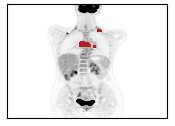

There has been growing research interest in using deep learning based method to achieve fully automated segmentation of lesion in Positron emission tomography computed tomography(PET CT) scans for the prognosis of various cancers. Recent advances in the medical image segmentation shows the nnUNET is feasible for diverse tasks. However, lesion segmentation in the PET images is not straightforward, because lesion and physiological uptake has similar distribution patterns. The Distinction of them requires extra structural information in the CT images. The present paper introduces a nnUNet based method for the lesion segmentation task. The proposed model is designed on the basis of the joint 2D and 3D nnUNET architecture to predict lesions across the whole body. It allows for automated segmentation of potential lesions. We evaluate the proposed method in the context of AutoPet Challenge, which measures the lesion segmentation performance in the metrics of dice score, false-positive volume and false-negative volume.